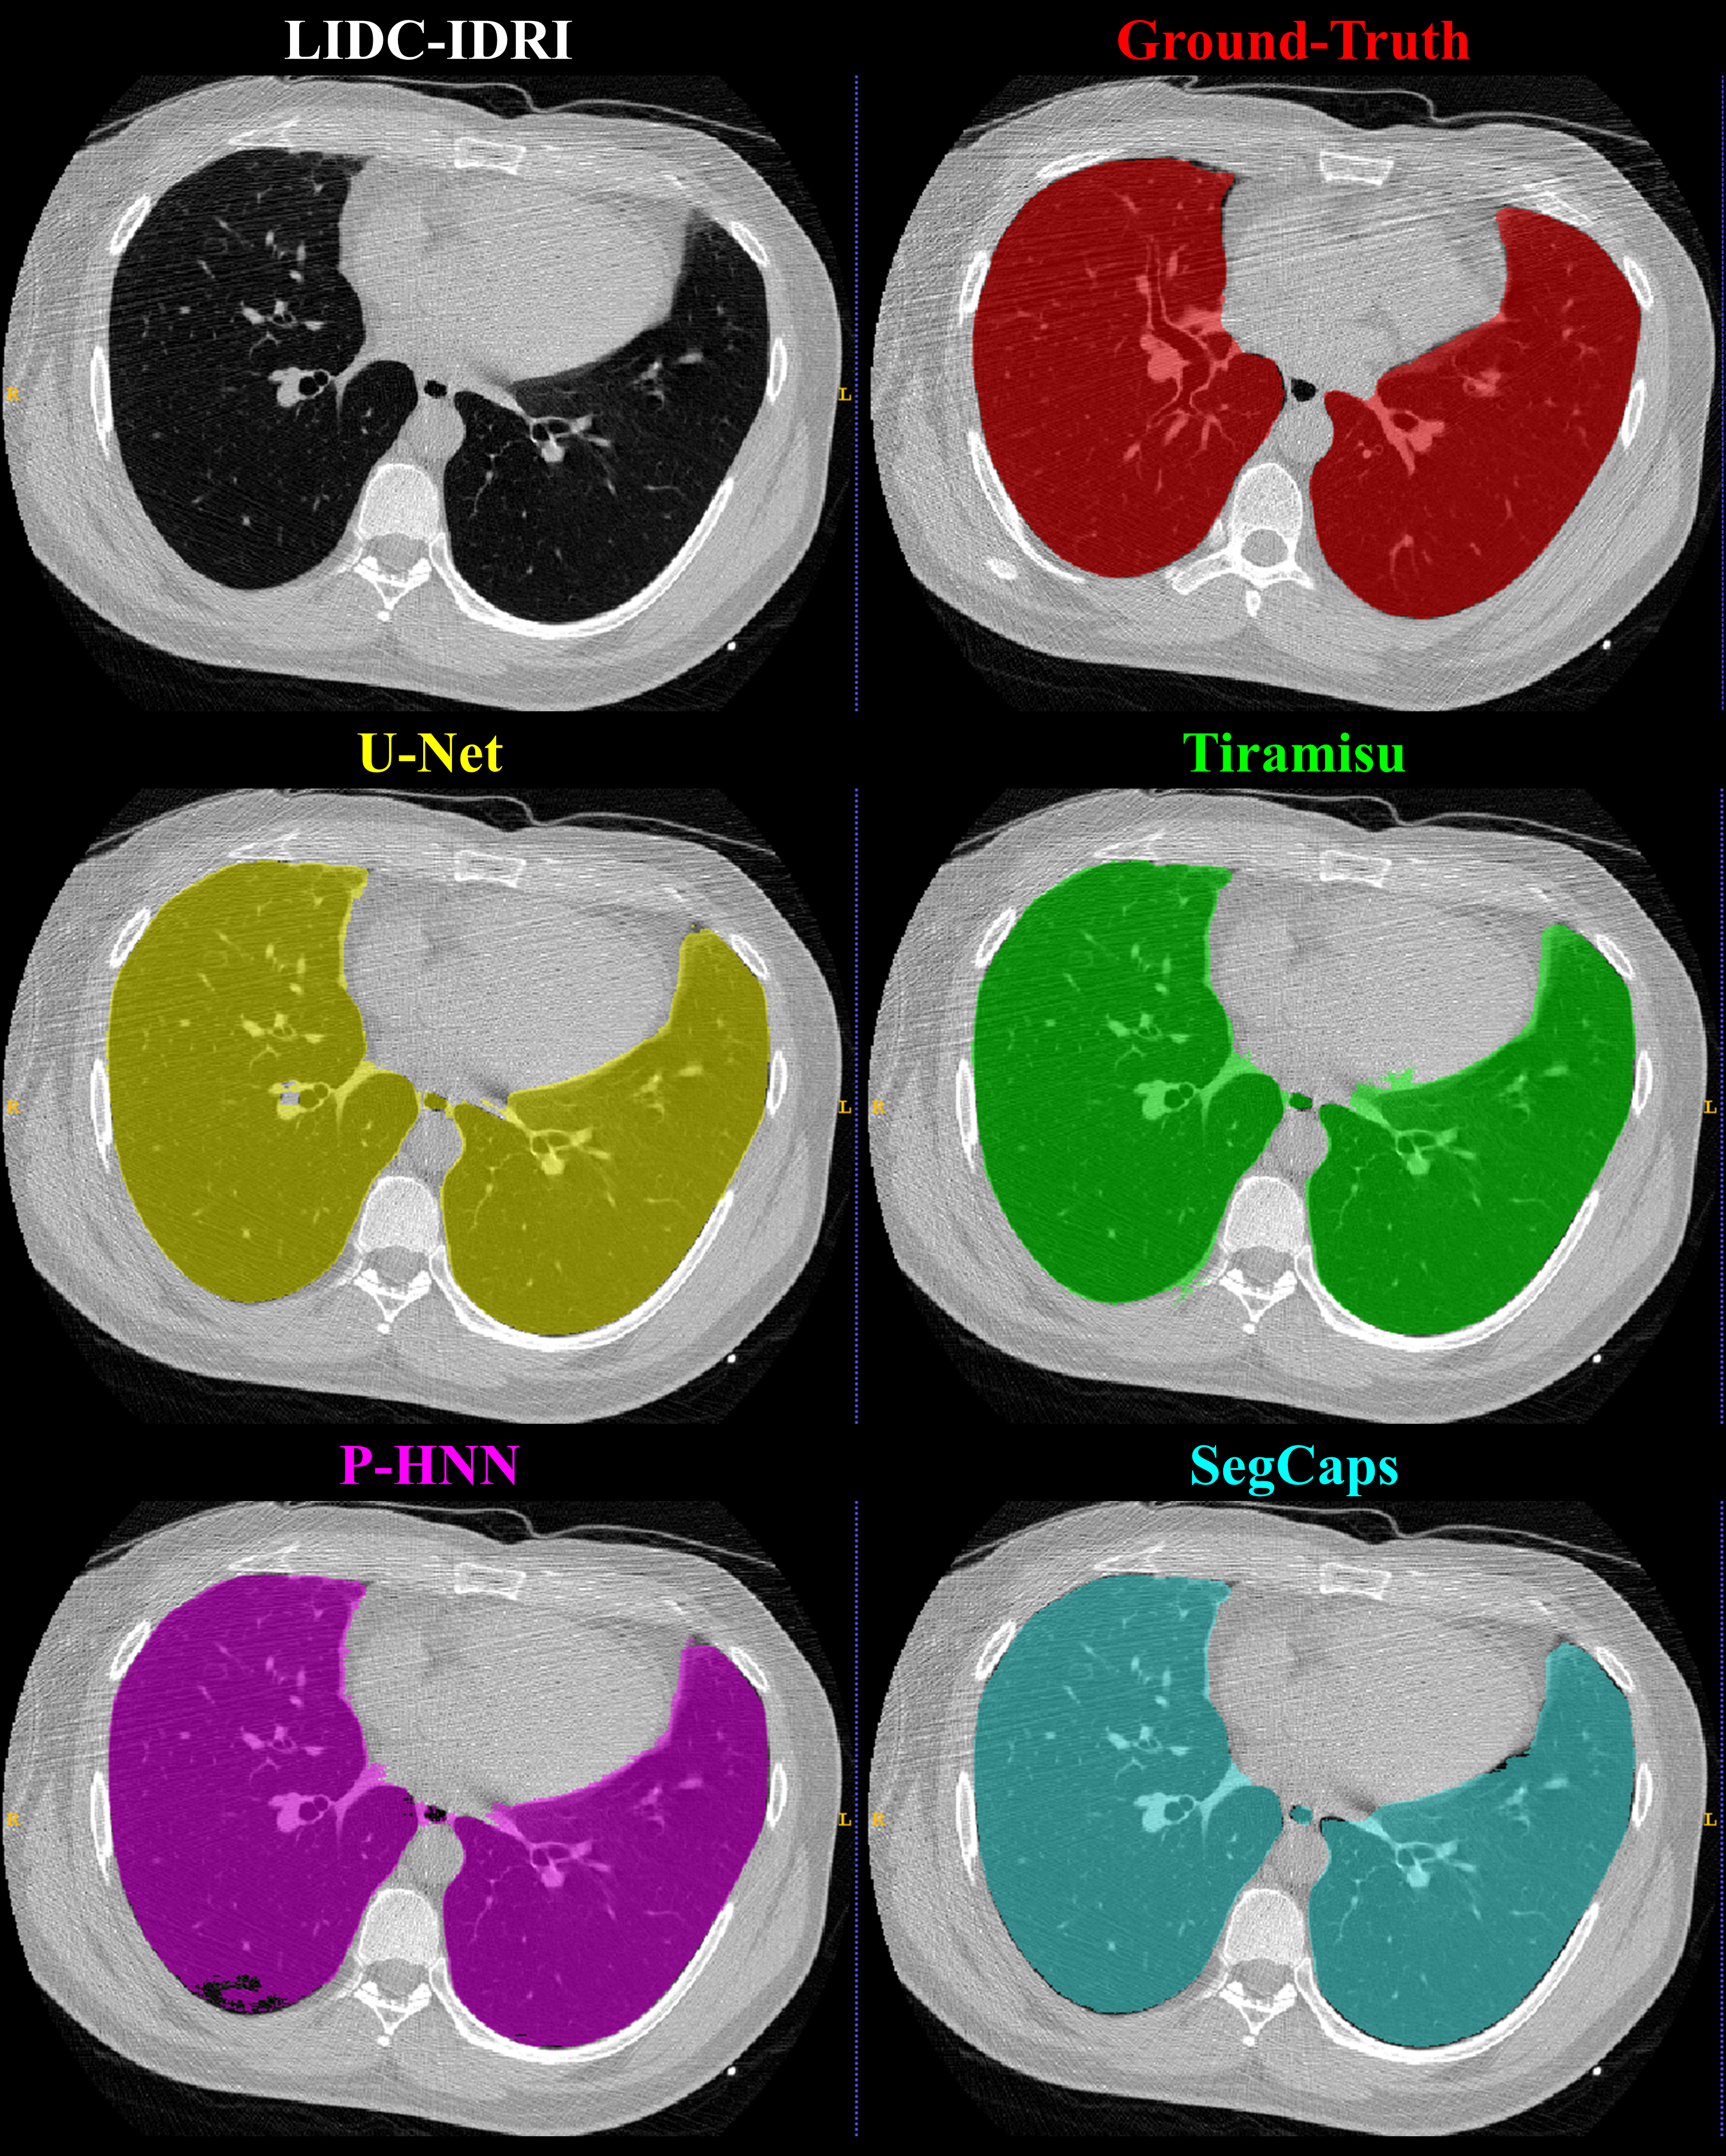

Refer to caption

Fig. 4: Qualitative results for a 2D slice from a CT scan taken from the LIDC-IDRI dataset. It can be noticed that the CNN-based methods’ typical failure cases are where the pixel intensities (Hounsfield units) are far from the class mean (i.e. high values within the lung regions or low values outside the lung regions).

Qualitative results for typical samples from all datasets are shown in Figure s 4 8. As can be seen in these qualitative examples, SegCaps achieves higher results by not falling into the typical segmentation failure causes, namely over-segmentation and segmentation-leakage. These qualitative examples are supported by our quantitative findings where over-segmentation is best captured by the HD metric and segmentation-leakages are best captured by the Dice metric.